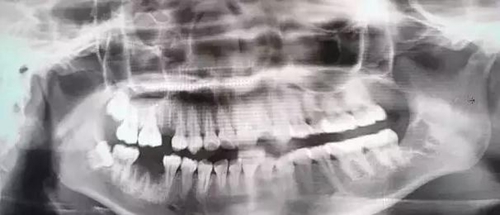

2.jpg

在拔牙前,需要通過檢查、問詢病史來評(píng)估,有的甚至需要拍片、抽血等,大概需要5~30min不等。

有臨床經(jīng)驗(yàn)的醫(yī)生還會(huì)根據(jù)你的實(shí)際情況(主觀意愿、經(jīng)濟(jì)承受能力、生理承受能力等),在控制風(fēng)險(xiǎn)的前提下綜合權(quán)衡,判斷你這顆牙是否建議拔除,盡可能為你選擇一個(gè)收益最高的方案。